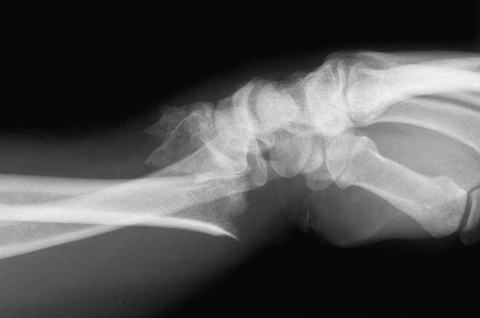

Case 1 Injury

Case 2 Preop

Case 3 Preop

Case3 Preop

Case 4 Preop

Case 5 Preop

Case 6 Preop

Case 7 Preop

Case 8 Preop